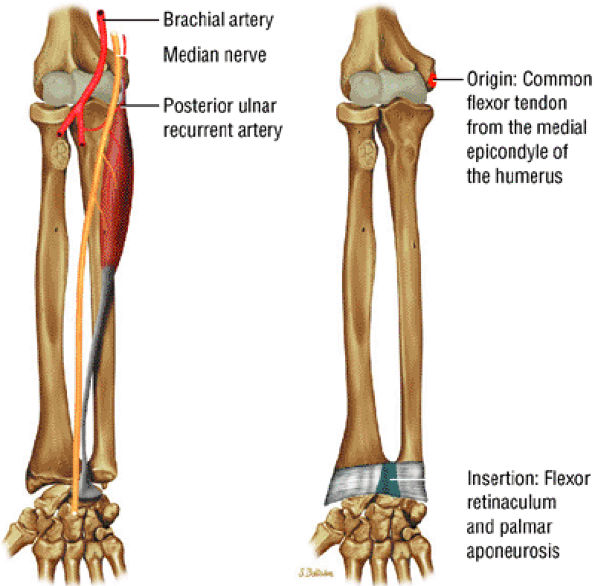

FIGURE 10.4 ● FLEXOR CARPI RADIALIS The flexor carpi radialis lies radial to the palmaris longus and ulnar to the pronator teres throughout its course. It contributes to flexion and abduction of the wrist. Distal flexor carpi radialis tendon rupture, usually occurring after a fall on the outstretched hand, can clinically mimic a scaphoid fracture.